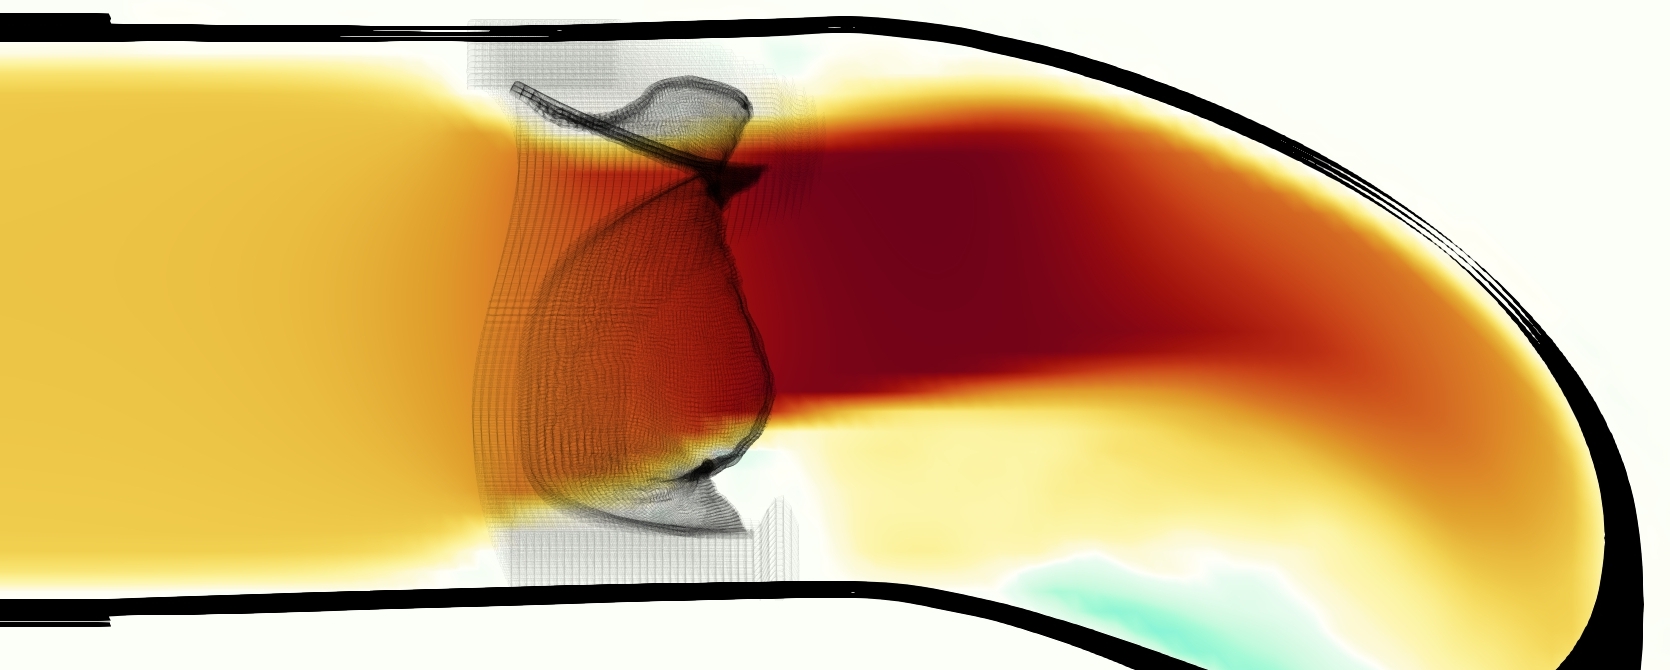

The emergent hemodynamics showed excellent qualitative agreement with experiments. Slice views of the axial component of fluid velocity ( component) in the sagittal plane that cuts through the center of the vessel, parallel to the flow direction, are shown in Figure 5. The flow in both the simulation and the experiment began to accelerate at the same time, with a jet forming through the open valve leaflets. The velocity, angle, and shape of the jet agreed well between the two cases during systole. The simulation captured the slight upward angle of the jet, which was not fully centered in the vessel. It also matched the location where the jet impacts the wall and the slower speed of the jet as it turns with the MPA downstream. As the flow decelerated, the fluid along the interior curve of the vessel reversed first while forward flow persisted where the jet was strongest, as seen in both the simulation and experimental results.

In both the experiment and the simulation, a separation region of reverse flow developed along the interior curve of the vessel under the core jet through the valve. The reverse flow began to develop at the same time in the cardiac cycle and grows throughout systole. The simulation lacked reversed flow in the entire region where reversed flow was present in the experiment, but this region developed some flow separation and had much slower flow than elsewhere in the vessel. Thus, the simulation captured that this is a distinct region from the core jet through the valve opening. There was a smaller amount of slower and slightly reversed flow along the outer curve of the vessel, close to the valve annulus and scaffold support. This region was well-matched between the experiment and the simulation.

Slice views of the (axial) component of fluid velocity in the axial plane, orthogonal to the flow direction, show that the simulation replicated the development of the jet over the cardiac cycle. At each phase, the simulation matched the forward speed of the core of the jet and the locations of reverse flow back towards the valve annulus. While there are some differences in the shape of the jet at certain phases and locations, the simulation clearly produced the general dynamics of the cardiac cycle that are seen in the experiment.

A comparison between the phase-averaged velocity resampled onto the MRI grid, the phase-averaged velocity without resampling, the instantaneous flow field without resampling and the MRI velocity field is shown in Figure 8. The coarser resolution is visible as a “stair-stepping” or “pixelated” effect on the phase-averaged resampled velocity, whereas the edges of the jet are more smooth in the phase-averaged velocity with no resampling. Otherwise, the resampled velocity appears qualitatively similar to the phase-averaged velocity with no resampling. Fine scale features were present in the instantaneous field that were lost in the phase-averaging and resampling process. There was more variation in the local velocity of the center of the jet and local areas of high velocity at the edges of the jet that suggested vortices. Vortical structures adjacent to the jet and in the areas of reversed flow were apparent. These comparisons suggest that 4D flow MRI data may lose substantial fine-scale flow features in the flow field via phase-averaging.

The simulated velocity fields showed excellent qualitative agreement with the experimental velocity. Many features of the flow that were present in the experimental measurements also appeared in the simulations, including a large jet which angled up downstream of the valve and the appearance of a triangle-like shape in the jet. A recirculation zone appeared downstream, though the precise region of recirculation showed only some agreement at some points in time. We prescribed the experimentally measured pressures (subject to minor processing as described in Section 3.3), and the emergent flow rates matched those of the experiments.

The phase-averaged, resampled velocity fields during peak systole and flow rates at each resolution are shown in Figure 10. Despite the limitations discussed above, we observe similar qualitative trends in the flow field at all resolutions. At all resolutions, a jet formed and angled up downstream of the valve orifice, as shown in the sagittal view. The jets showed a triangle-like cross section at with points aligned with the commissures. At cm, the jet appears like a rounded triangle in the opposing orientation, with its points aligned with the center of the leaflets. At cm, the jet is narrower downstream of the commissures, and wider downstream of the leaflets, again with a triangle-like cross section. The area of the jet increased with resolution, as expected given the IB method thickening of the valve structure. The narrowed jets at the two more coarse resolutions show locally elevated velocities relative to the two more fine resolutions. Figure 11 shows the instantaneous velocity fields at each resolution in the same axial and sagittal views. At 0.9 mm, the sagittal view shows a qualitatively different jet than at finer resolutions, with regions of lower velocity farther from the vessel wall, indicating insufficient resolution. At 0.9 and 0.68 mm, the jet is visibly narrowed compared to higher resolutions. While some features are similar at these two coarse resolutions, we conclude that the narrower jets indicate these simulations are under-resolved. Flows in the three finest resolutions, 0.45, 0.34 and 0.28 mm. appeared qualitatively similar, with slightly more fine structure detail in both the axial and sagittal views present at the edges of the jet. The jets in the axial views all showed a similar triangle-like cross section, slightly narrower downstream of the commissures, as in the phase-averaged fields. In both the phase-averaged and instantaneous fields, the three finest resolutions appear sufficiently similar that the conclusions of this study would be identical with any of these resolutions.